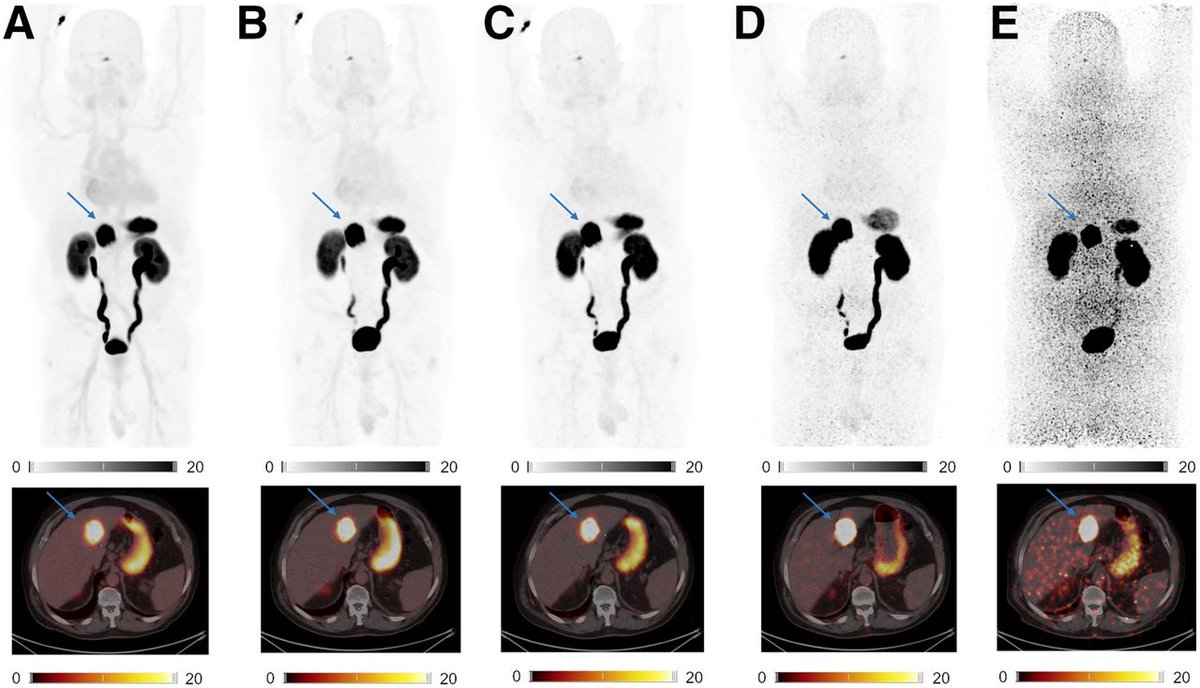

Active primary sclerosing cholangitis (PSC) is associated with elevated FAP expression, up to the level of cholangiocarcinoma. FAPI PET/CT may be used for the assessment of PSC activity. https://t.co/X9lNX7Jgic

#PETscan #NuclearMedicine #MedicalImaging @HeinerWedemeyer